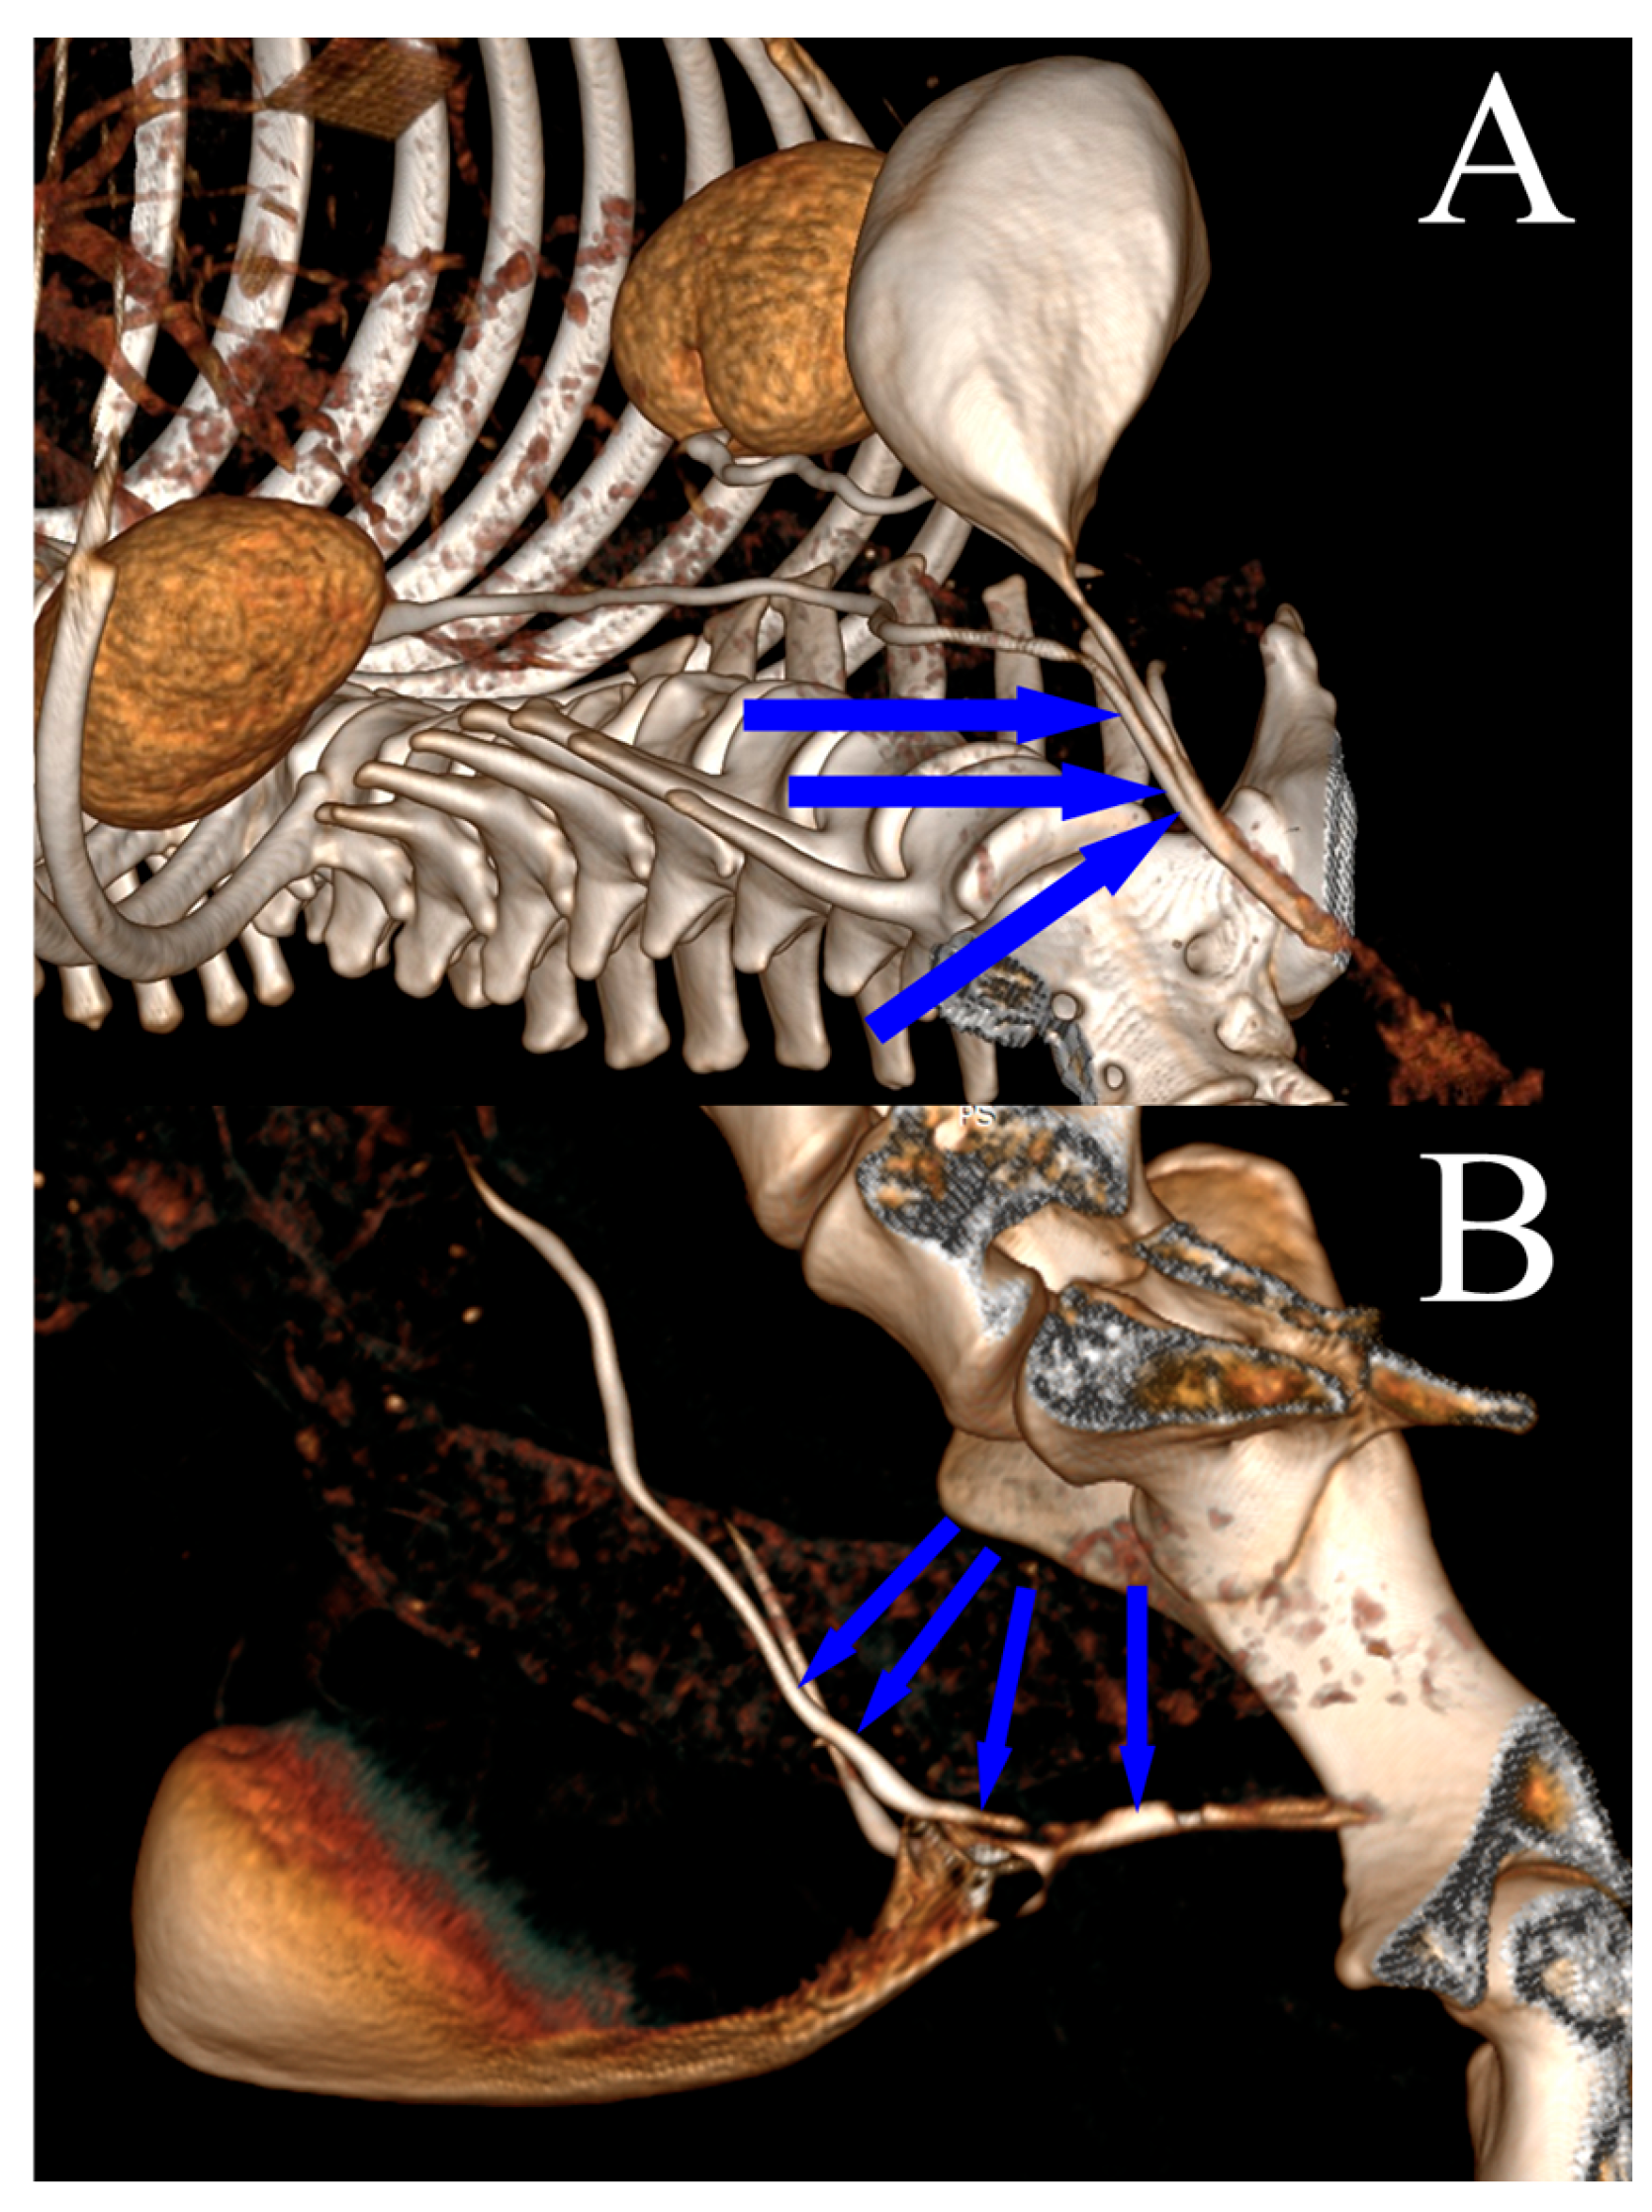

The female dogs were placed in dorsal recumbency. The skin around the vulva was scrubbed and disinfected with a chlorhexidine solution, and sterile surgical drapes were applied. A rigid ureteronephroscope was inserted into the bladder chamber and ureteral orifice in a retrograde manner, utilizing manual irrigation with saline (0.9% NaCl) solution. An examination of the ureterovesicular junctions was performed, the ectopic ureters were identified, and their locations were confirmed (Figure 2A). A laser fiber (272 μm Hol:YAG—Quanta System, Samarate, Italy) was then inserted into the ectopic ureteral opening through the working channel of the ureteronephroscope (Figure 2B). To correctly angle the tip of the laser fiber with respect to the medial aspect of the ectopic ureteral wall, the tip was deflected toward the urethral lumen. Subsequently, in a pulsating manner, the ectopic ureteral wall was carefully transected at the medial aspect using the Hol:YAG laser. This procedure was considered complete once the orifice of the ureter was within the lumen of the urinary bladder (Figure 2C).

Figure 2. Cystoscopic images of an intramural ectopic ureter in a female dog: (A) the ectopic ureter opening into the urethra, indicated by the arrow; (B) image captured during cystoscopically guided laser ablation of the ectopic ureter; and (C) image captured after cystoscopically guided laser ablation of the ectopic ureter wall.